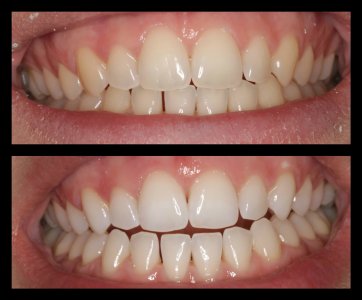

ΛΕΥΚΑΝΣΗ ΔΟΝΤΙΩΝ

ΠΡΟΣΘΕΤΙΚΕΣ ΑΠΟΚΑΤΑΣΤΑΣΕΙΣ ΜΕ ΣΥΝΔΥΑΣΜΟ ΛΕΥΚΑΝΣΗΣ, ΣΥΝΘΕΤΩΝ ΡΗΤΙΝΩΝ ΚΑΙ ΟΛΟΚΕΡΑΜΙΚΩΝ ΟΨΕΩΝ ΚΑΙ ΣΤΕΦΑΝΩΝ